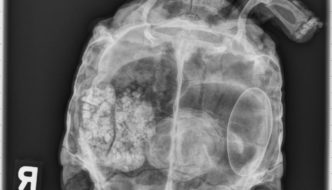

43 year old Desert Tortoise

Today's case is a 43-year-old female Desert Tortoise presenting today for anorexia and extended hibernation. Take a look and post your comments! … [Read more...]